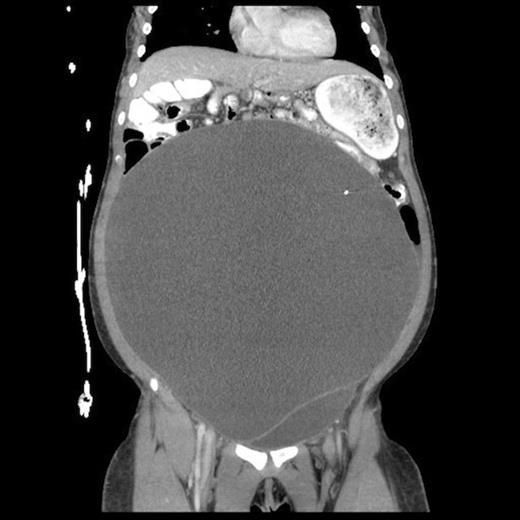

Abdominal CT, axial view, demonstrating a large fluid compartment surrounding the VP shunt catheter resulting in mass-effect, hydronephrosis, and displacement of the intra-abdominal contents

She eventually sought medical attention when she began developing diffuse, unremitting bilateral lower quadrant pain as her abdomen continued to enlarge (Fig. 1). A urine pregnancy test on admission was negative. Abdominal CT demonstrated a large fluid compartment surrounding the VP shunt catheter resulting in mass-effect, hydronephrosis, and displacement of the intra-abdominal contents (Fig. 2 and 3), establishing a diagnosis of APC.